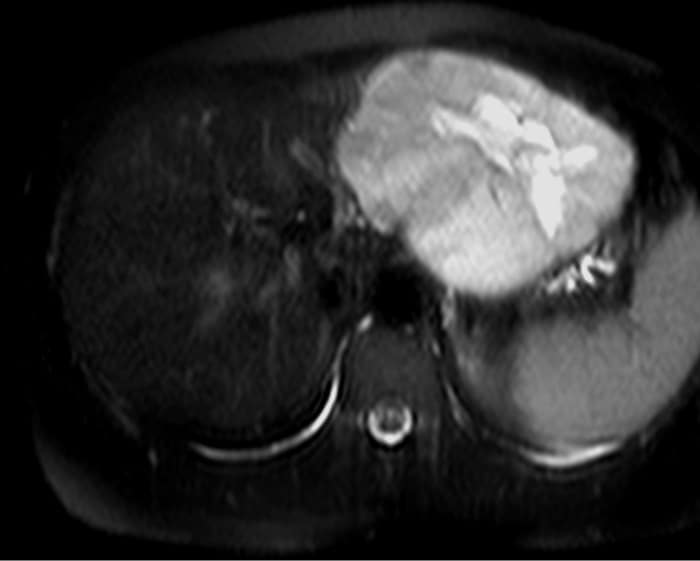

U máu gan

» Thông tin: Nữ giới – 47 tuổi.

» Lâm sàng: Đau thượng vị.